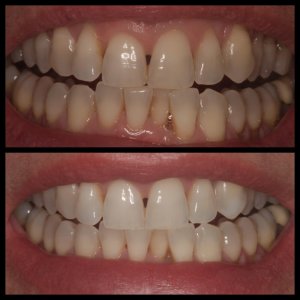

ΛΕΥΚΑΝΣΗ ΔΟΝΤΙΩΝ

ΠΡΟΣΘΕΤΙΚΕΣ ΑΠΟΚΑΤΑΣΤΑΣΕΙΣ ΜΕ ΣΥΝΔΥΑΣΜΟ ΛΕΥΚΑΝΣΗΣ, ΣΥΝΘΕΤΩΝ ΡΗΤΙΝΩΝ ΚΑΙ ΟΛΟΚΕΡΑΜΙΚΩΝ ΟΨΕΩΝ ΚΑΙ ΣΤΕΦΑΝΩΝ